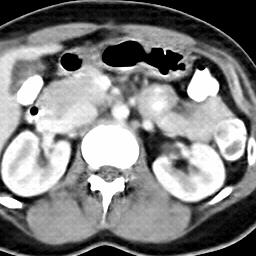

Due to the constraints of the imaging device and high cost in operation time, computer tomography (CT) scans are usually acquired with low intra-slice resolution. Improving the intra-slice resolution is beneficial to the disease diagnosis for both human experts and computer-aided systems. To this end, this paper builds a novel medical slice synthesis to increase the between-slice resolution. Considering that the ground-truth intermediate medical slices are always absent in clinical practice, we introduce the incremental cross-view mutual distillation strategy to accomplish this task in the self-supervised learning manner. Specifically, we model this problem from three different views: slice-wise interpolation from axial view and pixel-wise interpolation from coronal and sagittal views. Under this circumstance, the models learned from different views can distill valuable knowledge to guide the learning processes of each other. We can repeat this process to make the models synthesize intermediate slice data with increasing inter-slice resolution. To demonstrate the effectiveness of the proposed approach, we conduct comprehensive experiments on a large-scale CT dataset. Quantitative and qualitative comparison results show that our method outperforms state-of-the-art algorithms by clear margins.